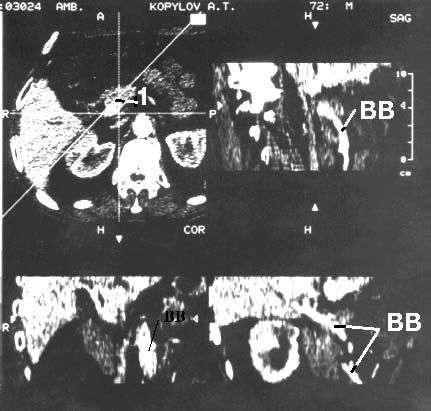

Локальная инвазия близлежащих висцеральных сосудов затрудняет и нередко делает невозможным выполнение резекции у большого числа больных РПЖ и поэтому дооперационной диагностике опухолевого прорастания сосудов, в особенности воротной вены, придается большое значение. В комбинации с внутривенным болюсным контрастированием и субтракционной обработкой данных, можно реконструировать СКТ-ангиограммы, воспроизводящие проекционные трехмерные изображения сосудистого русла и определить резектабельность опухоли с точностью 56–78 %. Считается, что результаты СКТ сопоставимы с таковыми при совместном применении КТ и ангиографии (рис. 100).

Рис. 100. Спиральная компьютерная томография с портографией. Рак головки ПЖ. На верхнем левом снимке видна гиподенсная бугристая опухоль головки ПЖ 4x5 см (1). На остальных снимках контрастирована воротная вена (ВВ). Отмечается ее прорастание в области опухоли